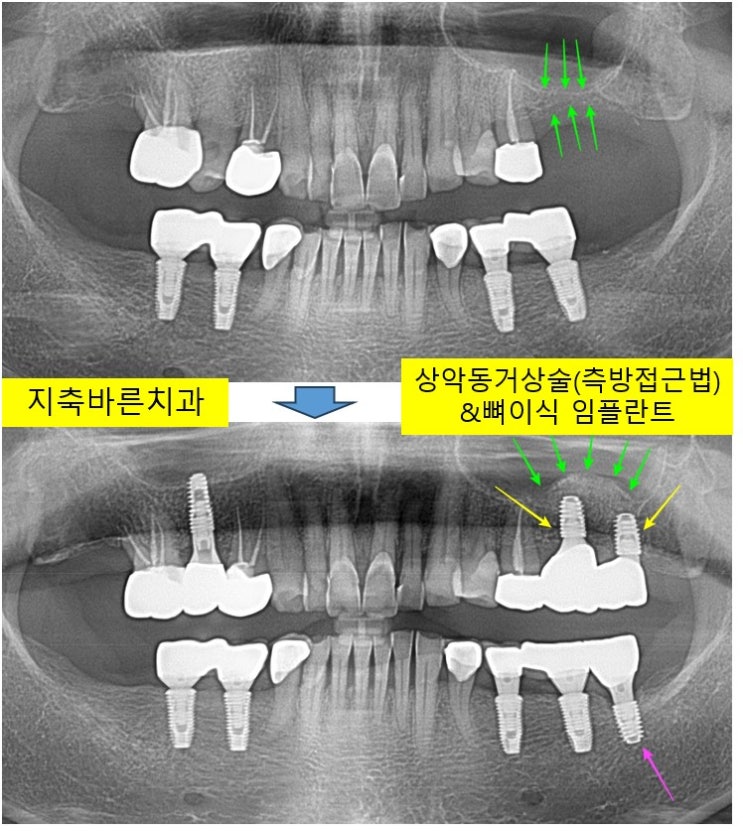

<상악동 거상술(측방 접근법) & 임플란트 식립 & 뼈이식>지축치과 지축역치과 삼송치과 원흥치과 원당치과 화정치과 정발산치과 파주치과 금릉치과 홍제치과 탄현치과 백마치과 양주치과6

왼쪽 어금니가 없어서 식사가 불편하시다고, 2023년 12월 60대 Jㅁㅁ 님께서 내원해주셨습니다. 1. 정확한...